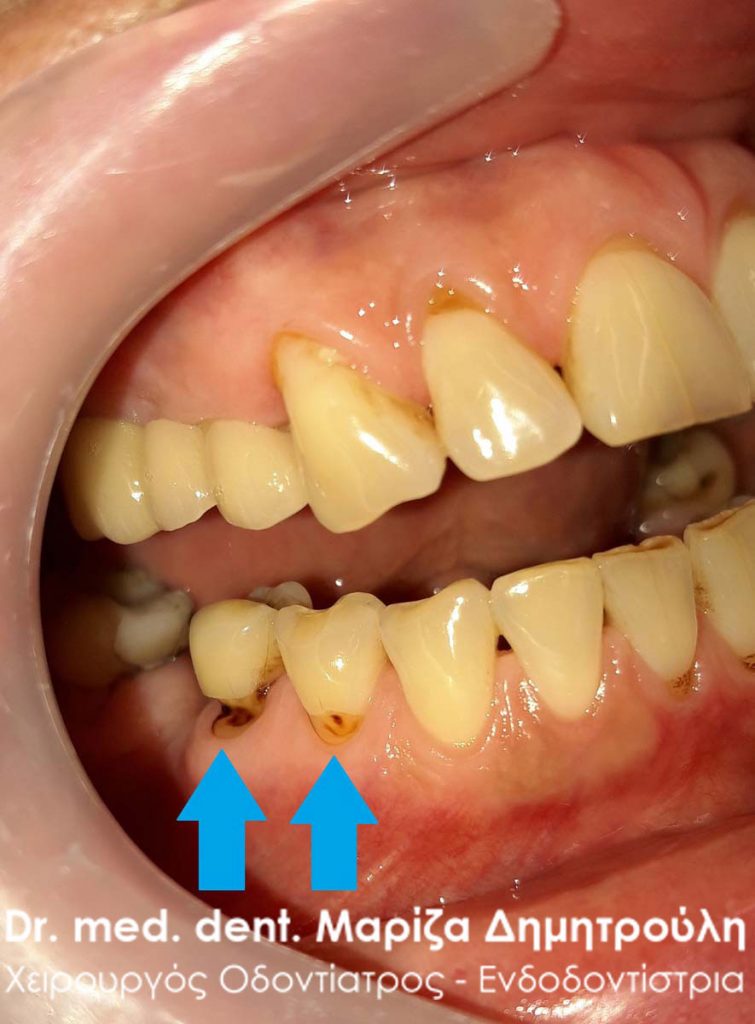

Αυχενικές αλλοιώσεις σε δόντια

Οι αυχενικές αλλοιώσεις είναι βλάβες που εμφανίζονται στον αυχένα του δοντιού και έχουν τη χαρακτηριστική μορφή του «ξαπλωμένου» μισοφέγγαρου. Στην ουσία πρόκειται για αποτριβές του σμάλτου των δοντιών. Η πιο συχνή αιτία που προκαλεί αυτές τις αποτριβές είναι το συχνό και έντονο / νευρικό βούρτσισμα των δοντιών με σκληρή οδοντόβουρτσα. Ο ασθενής στην προσπάθεια του να καθαρίσει όσο το δυνατόν καλύτερα τα δόντια του, τα τρίβει έντονα προκαλώντας σιγά – σιγά την αποτριβή του σμάλτου των δοντιών. Καθώς ο σμάλτος των δοντιών (αδαμαντίνη) φθείρεται, αποκαλύπτεται μέσα στο στόμα η οδοντίνη του δοντιού (κατώτερο μαλακό τμήμα του δοντιού) και ο ασθενής αρχίζει να παραπονείται στον οδοντίατρο για ευαισθησία στα δόντια.

Ένας άλλος επιβαρυντικός παράγοντας, που επίσης μπορεί να προκαλέσει τις αυχενικές αλλοιώσεις των δοντιών, είναι το τρίξιμο / σφίξιμο δοντιών. Όταν ένας ασθενής σφίγγει τα δόντια του με το πέρασμα του χρόνου στο στόμα του κάνουν την εμφάνισή τους οι υφιζήσεις των ούλων. Συχνά λοιπόν οι υφιζήσεις των ούλων είναι πιθανό να συνοδεύονται με αυχενικές αλλοιώσεις, χωρίς βέβαια αυτό να αποτελεί τον κανόνα.